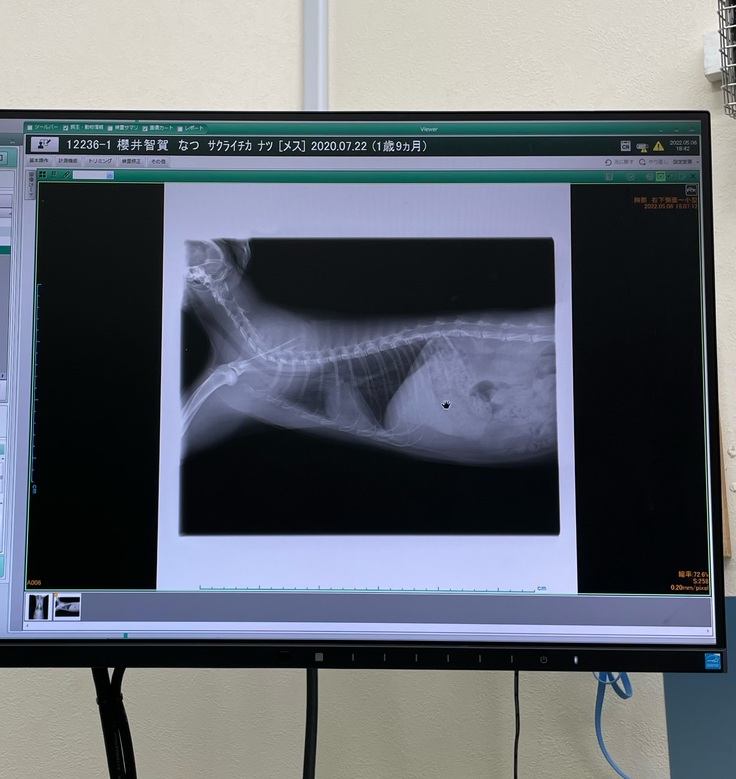

検査が終わり、レントゲンを見せられ胸水が溜まっていることを告げられ、いつ呼吸が止まってもおかしくないとの事で、すぐに胸水を抜いてもらいました。見せてもらった胸水は200ccもありました。

5/6 血液検査1回目

投薬から2週間経つので、オノデラ動物病院さんにてエコー検査、血液検査をしました。

胸水・腹水は消え血液検査の結果も良好との事でした。

血液検査結果です↓

レントゲン検査結果です。

▼4/22 (投薬前)

▼5/6 (投薬後)